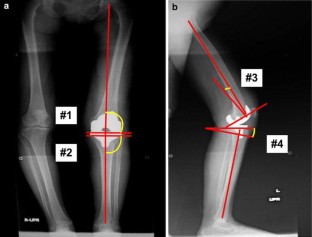

A total of 173 patients underwent primary TKA. In 76 TKAs, we used the bony landmark method, and in 97 TKAs, we used the conventional method. In the bony landmark method, we set the coronal alignment in reference to the line connecting the proximal and distal one-third of the anterior tibial border, and we determined the 5° posterior slope in reference to this line. Six months postoperatively, radiological evaluations were performed using full-length standing anteroposterior and lateral radiographs of the knee.

Fig. 1

Fig. 2